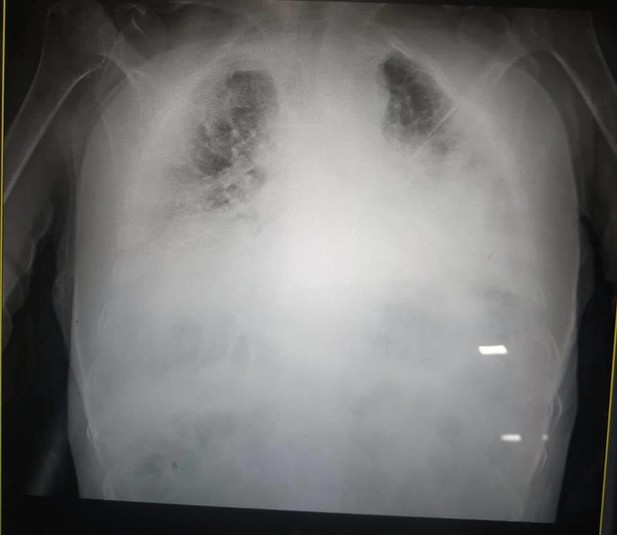

«Це одні з найстрашніших легень, які я бачила в житті», – сказала очільниця реанімації

Львівські лікарі показали фото, як виглядають легені у пацієнтів, які мають тяжкий перебіг коронавірусу.

«Це одні з найстрашніших легень, які я бачила в житті», – сказала мені щойно очільниця реанімації клінічної лікарні швидкої медичної допомоги Львова», – розповіла журналістка.